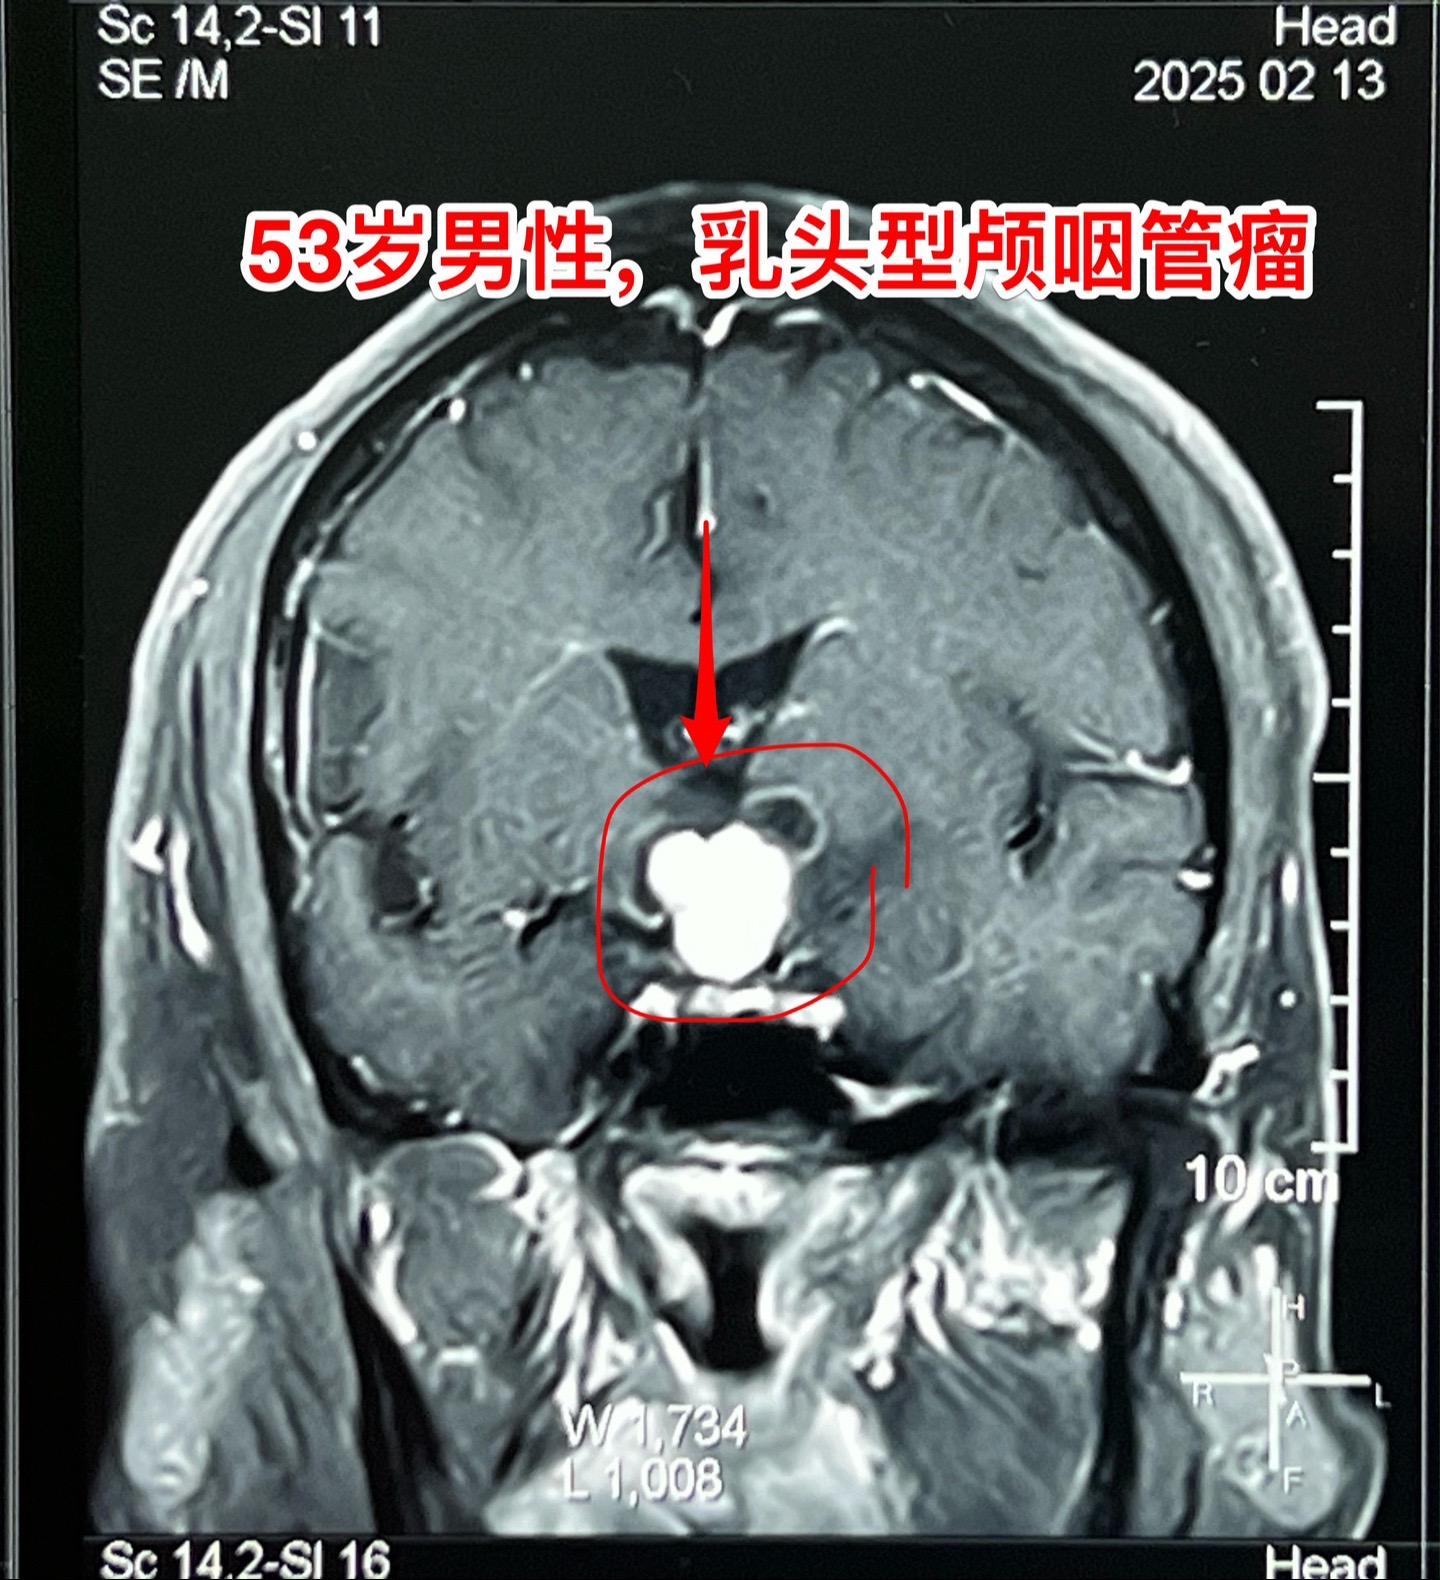

一天两个颅咽管瘤手术医生是很辛苦的 今天按计划作了两个颅咽管瘤手术。这是第二个病人,云南省文山州的警察,因记忆力差、爱睡觉、视力下降到医院检查发现了颅咽管瘤,是乳头型颅咽管瘤。 今天晚上九点多钟颅咽管瘤完全切除了,同时发现前交通动脉有个小动脉瘤,征得家人同意后作了动脉瘤夹闭术。期望病人一切都好!